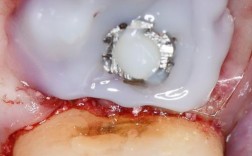

基台连接与取模:

- 骨结合完成后,医生会进行二期手术(有时是微创方式),暴露种植体顶部,连接基台(连接种植体和牙冠的中间部件)。

- 然后取模,制作最终的牙冠(通常为全瓷冠)。